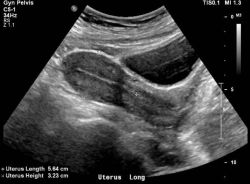

На какой день делать УЗИ малого таза? Что показывает УЗИ малого таза у женщин?

Организм женщины представляет собой хрупкий и тонко устроенный механизм, который требует постоянного ухода и внимания. У многих возникает вопрос о том, как можно проверить происходящие в организме изменения, а также состояние тех или иных органов. В данном вопросе на помощь женщине может прийти специалист по диагностике с помощью ультразвука.

Когда лучше делать УЗИ малого таза? Что показывает УЗИ малого таза

В данной статье разберемся, что показывает УЗИ малого таза. Организм женщины можно сравнить с крайне хрупким механизмом, который требует постоянного внимания и ухода. Но определить возможные изменения, происходящие в теле, понять, все ли органы работают в штатном режиме или требуется обратить внимание на состояние той или иной системы в организме, возможно с помощью аппарата ультразвукового исследования.